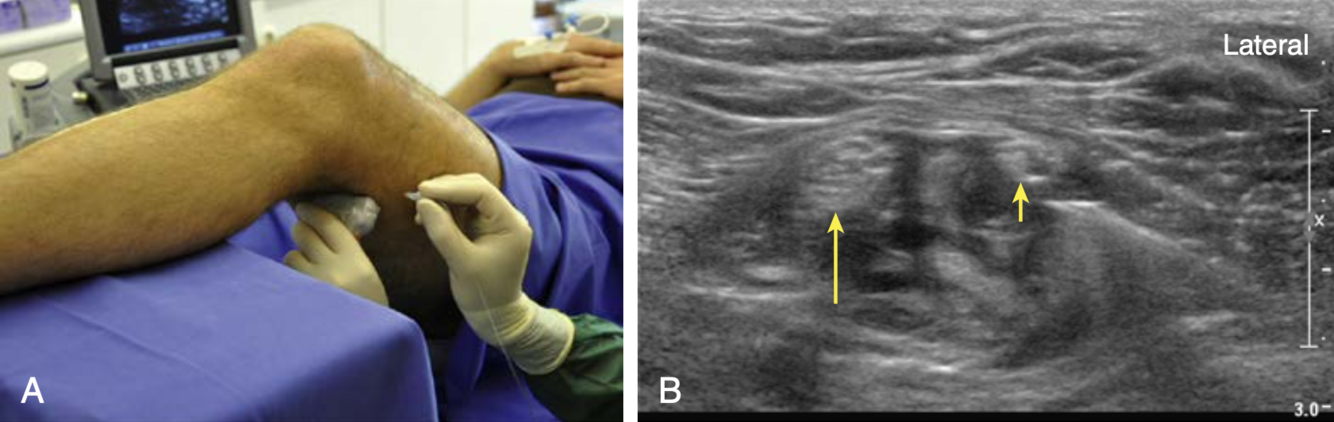

Quais os nervos apontados pelas figuras?

• flecha longa: tibial

• flecha curta: fibular comum

Identificar as estruturas conforme a imagem do bloqueio ciatico

* importante deslizar o US para visualizar a ramificacao, porque pode ocorrer de maneira mais proximal e ocorrer apenas o bloqueio do nervo Tibial * injetar 20ml para separar os nervos (aspecto de "doughnut")